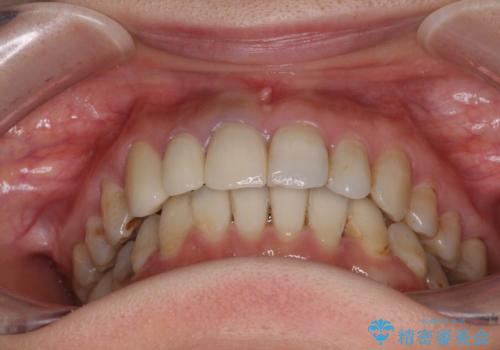

- 前歯の歯並びやむし歯治療の跡、奥歯の銀歯を気にして来院された患者様です。

インビザラインによる矯正治療の後に虫歯や銀歯をセラミックにて補綴することとしました。

前歯のむし歯治療の跡や奥歯の目立つ銀歯がなくなり、明るい口元になりました。